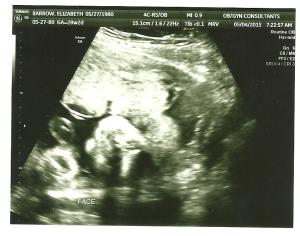

If you look closely, you will see a smooshed baby face turned sideways and two little fists below the face….hello baby Luke!

(Another face shot. Sideways. Ultrasounds are creepy.)